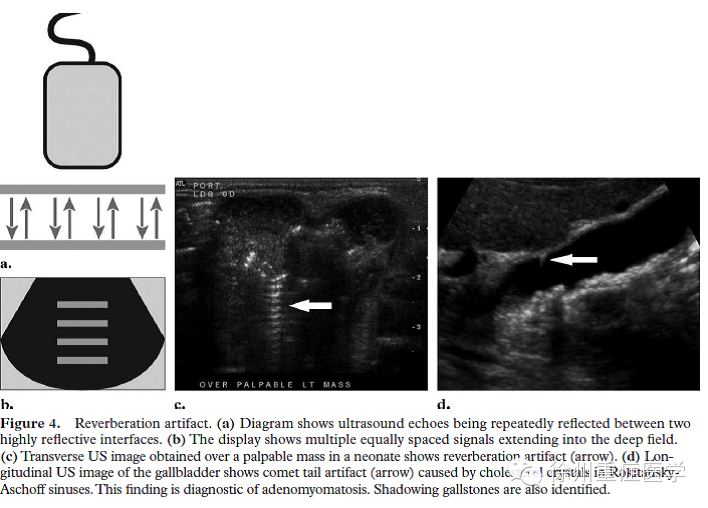

超声发射声波并接收物体的回波,并通过声波往来的时间计算物体的深度。在两个平行的反射界面中,超声波可以来来回回地反射并被探头接收到(图 4a)。此时,多重反射的回波可以被机器记录和显示。第一个反射波显示在正确的位置。依次接收到的回波需要较长时间返回到探头,超声处理器按照探头回波的时间来增加相应的距离。图像中,这种线性等距间隔的多次反射,称为混响伪像(图 4b 4c)。

慧尾征是一种混响伪像,2个强反射体依次排列且相互靠近。声波在2个界面或靶器官内来回反射。图像上,连续的回波相互靠近且难以区分。另外,后来的声波可以逐渐衰减,并可以表现为声束宽度逐渐减少。慧尾征常见于三角形或圆锥形反射源。过去,振铃伪像被认为是特殊的慧尾征,因为2个伪像的图像非常相似。超声波在气体包绕的液体之间产生强烈的共振。这些振动产生连续的回波并传送回探头(图 5 d)。图像显示为发自气体向后延伸带状或或平行条带状。尽管类似的声像图表现,但这些两个产生机制并不相同。常见于肠道内气体或探头接触不良,也可在超声引导穿刺时用于穿刺针的定位。